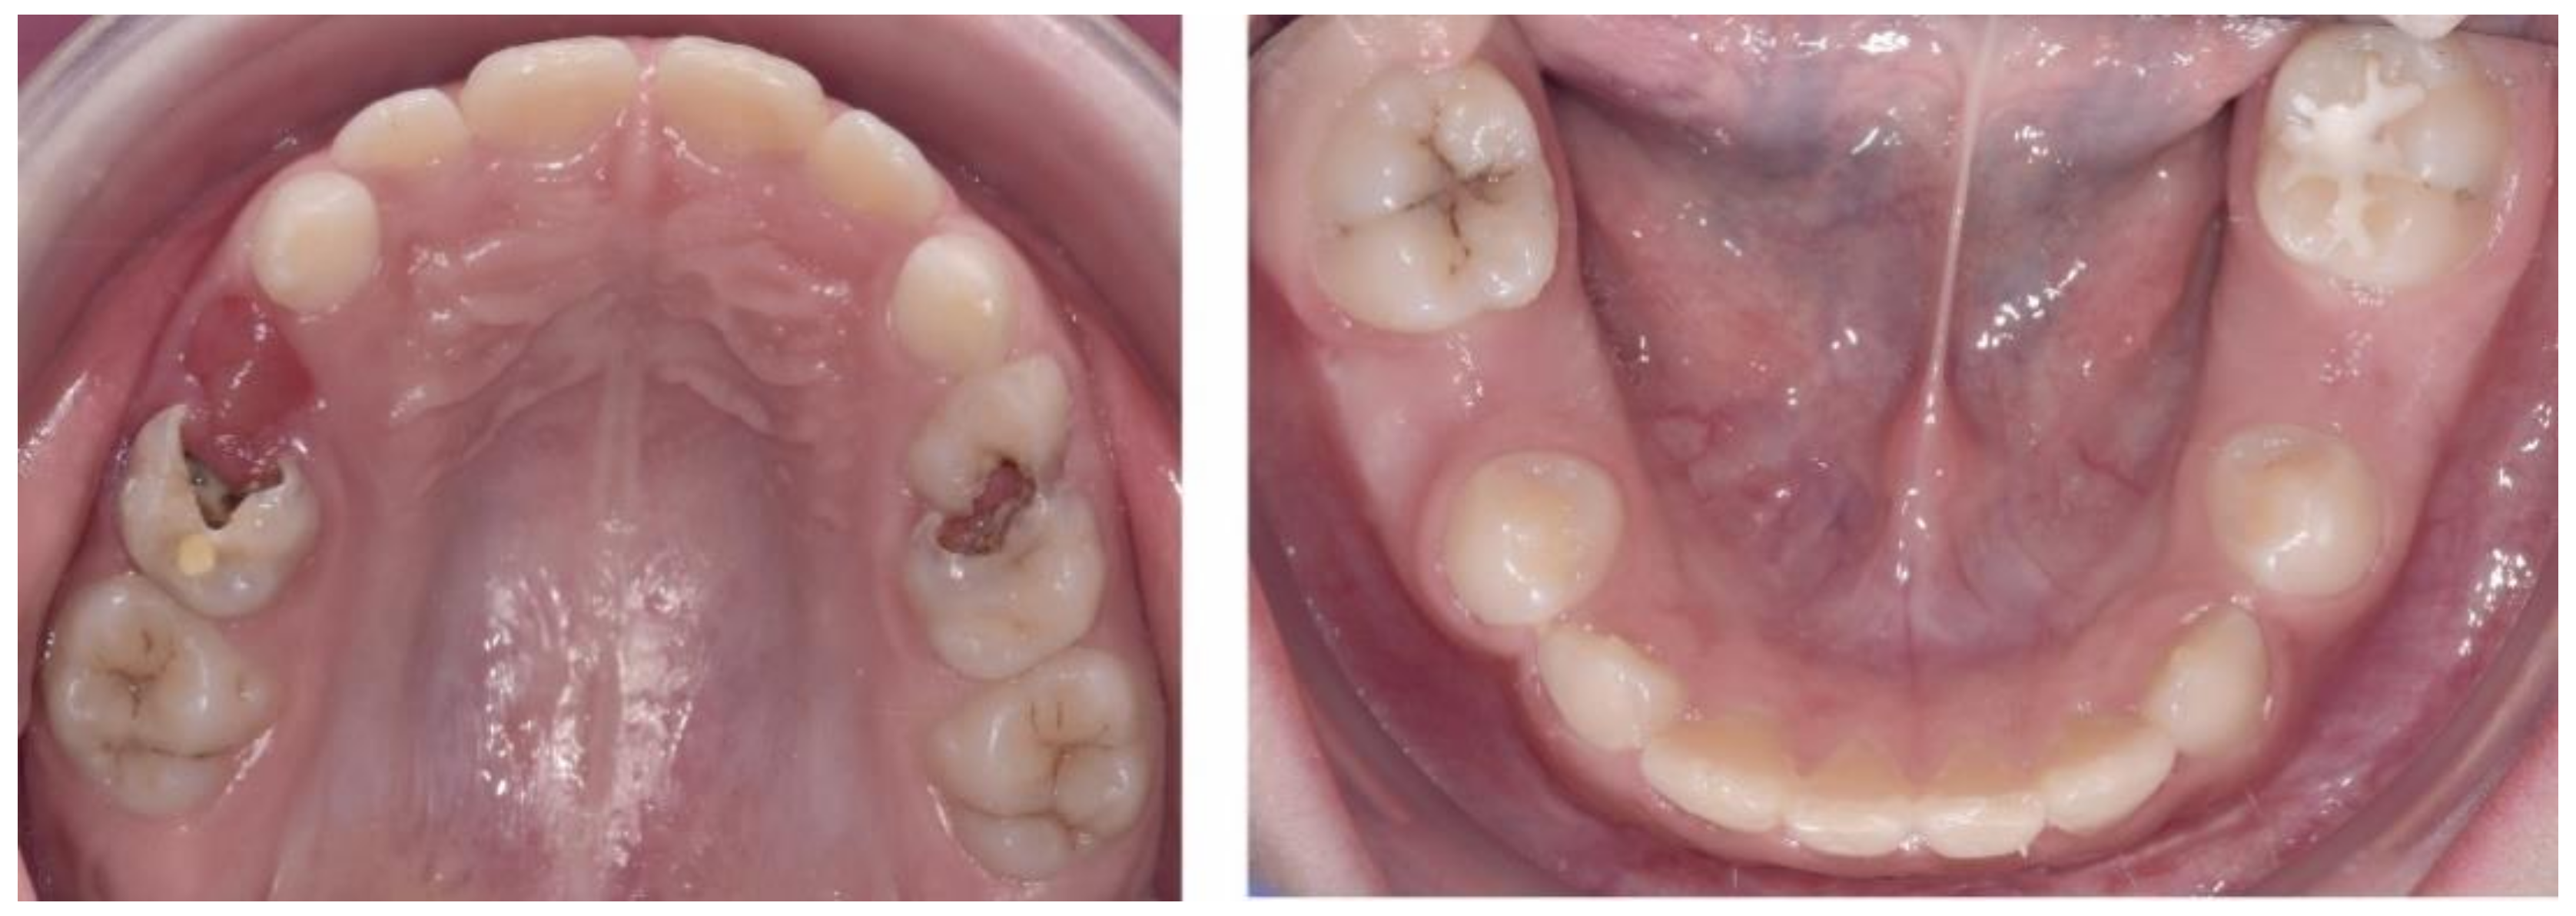

2.2.1. Initial Examination

2.3.2. Second Phase of Treatment—2017—Bite-Blocks and Transpalatal Arch